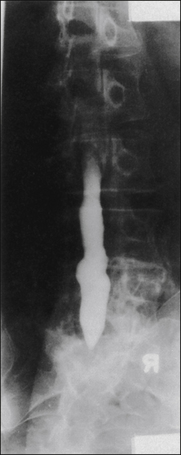

Arachnoiditis is an unusual problem if viewed as a clinical syndrome, not a radiological finding. Many patients who have undergone spinal surgery with or without myelography demonstrate root adhesions and adherence of nerve roots to the dural sac (Fig. 71-6). Most of these findings have no obvious clinical significance, but some do seem to be associated with symptoms. However, chronic adhesive arachnoiditis is rarely progressive and needs to be considered in some patients. Symptoms of this rare syndrome are diffuse lower extremity pain, often neuropathic in character, and slowly progressive loss of function.

Figure 71-6 Anteroposterior view of a myelogram carried out with a water-based agent and demonstrating the changes typical of epidural fibrosis and arachnoiditis.

The thecal sac is deformed laterally by an epidural scar from L3 to L5. No root sheaths are seen; roots are adherent to the dura, and no internal structures within the thecal sac are evident. This is a typical form of arachnoiditis. The patient’s complaints were of migratory pain involving different nerve roots at different times.